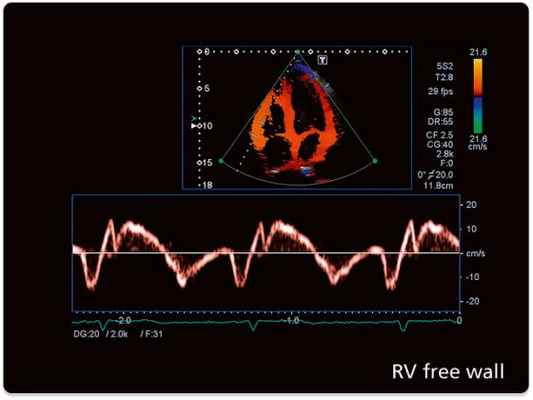

59. Miyatake K., Yamagishi M., Tanaka N. et al. New method for evaluating left ventricular wall motion by color-coded tissue Doppler imaging: in vitro and in vivo studies. J Am Coll Cardiol 1995;25:717– 724.

60. Tsutsui H., Uematsu M., Shimizu H. et al. Comparative usefulness of myocardial velocity gradient in detecting ischemic myocardium by a dobutamine challenge. J Am Coll Cardiol 1998;31:89–93.

61. Dandel M., Lehmkuhl H., Knosalla C. et al. Strain and Strain Rate Imaging by Echocardiography – Basic Concepts and Clinical Applicability. Current Cardiology Reviews 2009; 5: 133-148.

62. Marwick T.H., Cheuk-Man Yu., Jing Ping Sun. Myocardial Imaging: Tissue Doppler and Speckle Tracking. Oxford: Blackwell Publishing; 2007.

63. D’Hooge J., Heimdal A., Jamal F. et al. Regional strain and strain rate measurements by cardiac ultrasound: principles, implementation and limitations. Eur J Echocardiogr 2000; 1(3): 154-70.

64. Yip G.W., Ommen S.R. Tissue doppler imaging in coronary artery disease. Heart views 2002; 3(1):

65. Voigt J.U., Exner B., Schmiedehausen K. et al. Strain-rate imaging during dobutamine stress echocardiography provides objective evidence of inducible ischemia. Circulation 2003;107:2120–6.

66. Hoffmann R., Altiok E., Nowak B. et al. Strain rate measurement by doppler echocardiography allows improved assessment of myocardial viability inpatients with depressed left ventricular function. J Am Coll Cardiol 2002;39;443-449.

67. Hanekom L., Jenkins C., Jeffries L. et al. Incremental Value of Strain Rate Analysis as an Adjunct to Wall-Motion Scoring for Assessment of Myocardial Viability by Dobutamine Echocardiography: Follow-Up Study After Revascularization. Circulation 2005;112;3892-3900.